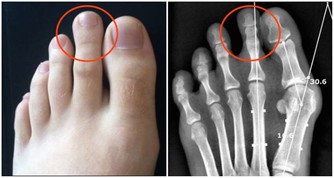

4、痛風石

痛風石的形成是長期高尿酸血症引起的組織損傷的結果,是痛風的特徵性病變;沉積在關節囊,影響關節活動;可導致骨“鑿孔”樣損害,嚴重者可導致骨折。關節脫位及畸形;痛風石破潰後,不易癒合,極易導致截肢悲劇。